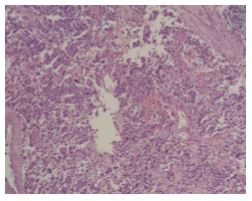

Histopathological diagnosis confirmed the suspicion of a well-defined and encapsulated paraganglioma measuring 2 x 1 x 0.3 cm, with a low mitotic index (< 2). Immunohistochemical staining was positive for chromogranin and synaptophysin (Figure 3).

Figure 3. Histopathological examination showing a well-defined and encapsulated paraganglioma measuring 20 x 10 x 3 mm